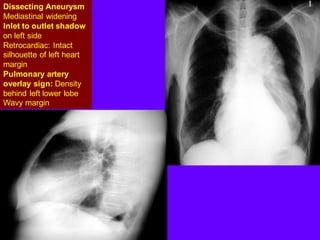

Dissecting Aneurysm

Mediastinal widening

Inlet to outlet shadow

on left side

Retrocardiac: Intact

silhouette of left heart

margin

Pulmonary artery

overlay sign: Density

behind left lower lobe

Wavy margin